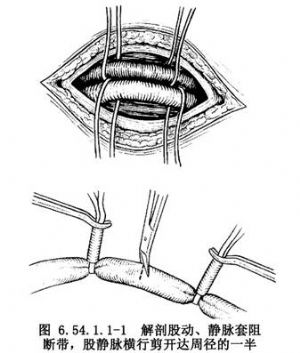

大腿稍外旋,自腹股沟韧带稍上方开始,沿股动、静脉走向,向远侧做10cm长纵行切口,解剖出股动、静脉并分别在其近、远侧绕阻断带暂时阻断血流。将股静脉横行剪开达周径之半(图6.54.1.1-1),插入有侧孔的F32~36号静脉导管,向近侧一直插入至下腔静脉,收紧阻断带,固定导管(图6.54.1.1-2)。并以适宜口径的导管做股动脉插管,导管尖端置于髂总动脉内。肝素化后开始部分转流(图6.54.1.1-3)。在流量仅达1000ml/min时病人情况即会明显改善,此时即可行全身麻醉气管插管。